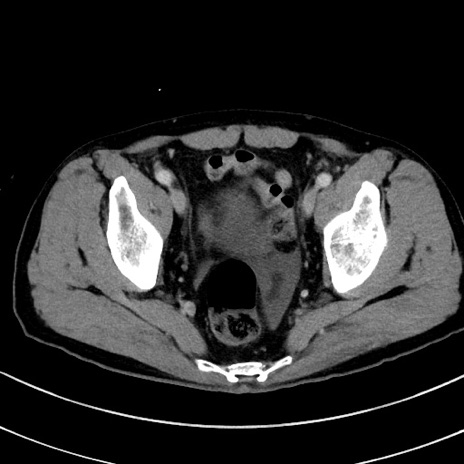

症例8(横断像)

【症例】 60歳代男性

【主訴】 黒色吐物

【現病歴】 4日前から嘔気自覚、2日前の朝食後にも嘔気あり、自分で手で嘔吐反射起こし嘔吐したところ血が混ざっていたため受診。

【既往歴】 5年前汎発性腹膜炎を伴う急性虫垂炎で手術、高血圧、前立腺肥大症、高脂血症

【身体所見】 腹部正中に手術癩痕あり 腹部平坦・軟圧痛なし膨満感あり

【データ】WBC 8400、CRP 4.54